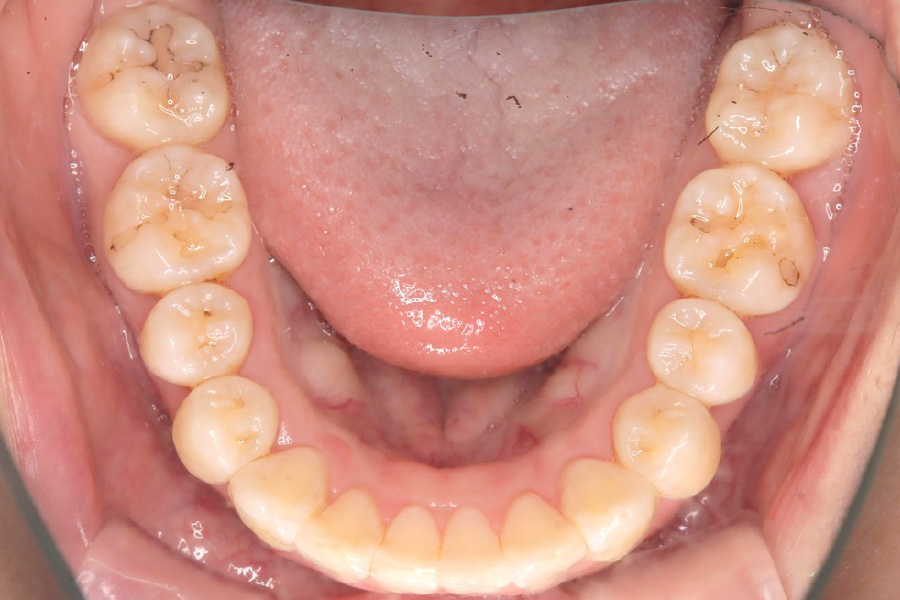

治療後

治療内容 インビザライン矯正

小臼歯抜歯

治療に伴うリスク 矯正終了後は、リテーナーを指示通りに使用し、歯の後戻りを防ぐ必要があります。